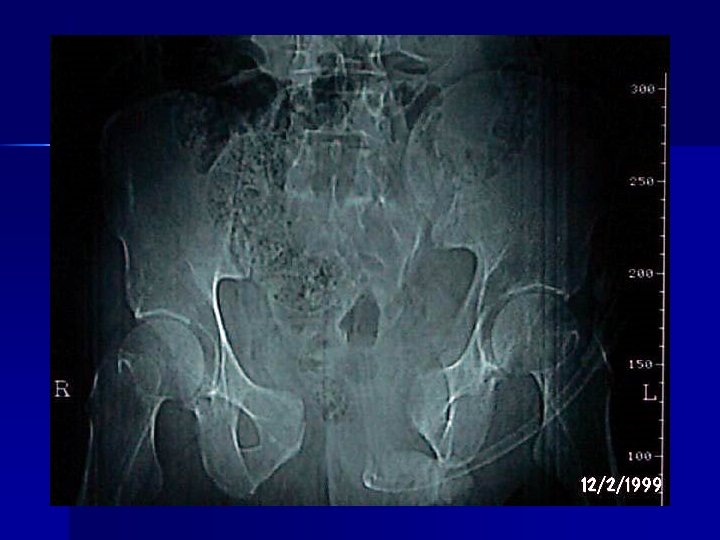

PELVIS n Ex Físico n Palpación ósea n Valorar genitales: Hematoma escrotal Hematuria o Uretrorragia n Palpación bimanual (mujer): Laceración vaginal Fx pélvica abierta

PELVIS Uretrografía retrógrada (antes de Sonda Foley) -Uretrorragia -Hematoma escrotal -Próstata cabalgante n Rx de pelvis: -Fracturas -Hematoma pélvico retroperitoneal -Pte inestable: TAC vs Cirugía n